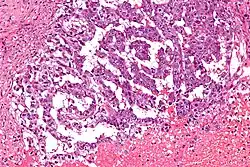

La tumeur du sac vitellin est une tumeur peu commune issue des cellules germinales qui reproduisent des structures extra-embryonnaires. Elle correspond à la tumeur maligne la plus fréquemment retrouvée chez l'enfant. Elle est caractérisée par une prolifération tumorale à cellules claires agencée en réseau et peut former des structures végétantes endoluminales. Cette tumeur est rarement bilatérale.